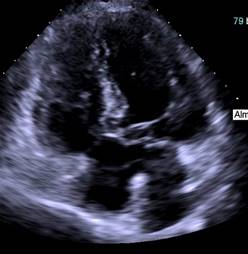

Se recibe en nuestra unidad con presión arterial 102/64 mmHg, frecuencia cardiaca 82 latidos por minuto, saturando 92% con ventilación continua mandatoria controlada por volumen (VMC-CVs) programada con un volumen tidal (VT) de 360 ml, PEEP 6 cmH2O, FiO2 60%, frecuencia respiratoria (FR) de 16. A la exploración física los únicos hallazgos patológicos fueron disminución del murmullo vesicular en base izquierda, con matidez a la auscultación, así como soplo sistólico en foco mitral. Por dichos hallazgos se realiza rastreo pulmonar ultrasonográfico, encontrando sólo atelectasia de lóbulo inferior izquierdo. Se realiza radiografía de tórax en donde se confirma atelectasia en dicha anatomía y además se evidencia adecuada colocación de tubo endotraqueal. Por la presencia de atelectasia se decide incrementar la PEEP hasta 10 cmH2O y posterior a 16 cmH2O por nula respuesta; sin embargo, con empeoramiento del cuadro manifestado por mayor requerimiento de FiO2 (100%) por desaturación de 70%, inestabilidad hemodinámica con requerimiento de vasopresor por tensión arterial de 70/40 mmHg, y bradicardia de 35 lpm que mejora con la administración de dosis única de atropina. Se sospecha de tromboembolia pulmonar (TEP), por lo que se realiza rastreo ecocardiográfico en búsqueda de hallazgos sugestivos ante una paciente hemodinámicamente inestable. Se encuentra en primer rastreo ultrasonográfico cardíaco patrón hemodinámico hiperdinámico caracterizado por signo del beso papilar del ventrículo izquierdo (VI), pero probable defecto del septum (Figura 1), a nivel pulmonar derrame pleural bilateral no evidenciado en radiografía de tórax.

Figura 1: Ecocardiograma transtorácico en donde se evidencia la presencia de probable defecto septal.